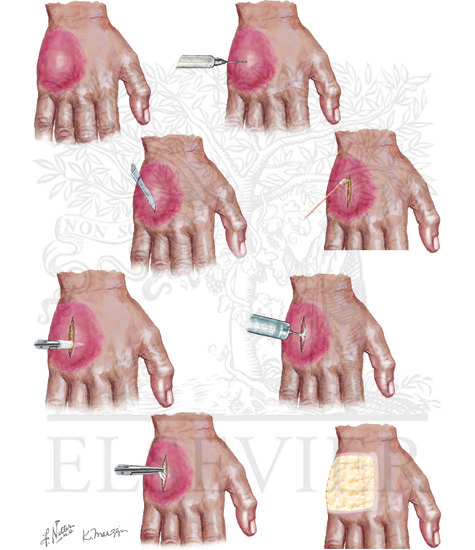

A Better Way to Drain Abscesses: The Berlin Technique | Jail Medicine

Skin Abscess Incision and Drainage